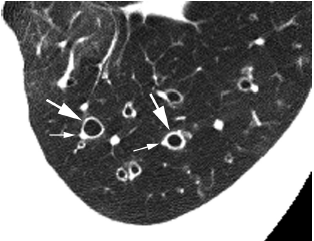

图3 支气管扩张患者

支气管扩张患者的左肺下叶HRCT 图像,显示许多“印戒征”实例,扩张的支气管( 大箭头) 和伴行的明显减小的肺动脉( 小箭头) 形成印戒征,支气管管壁增厚